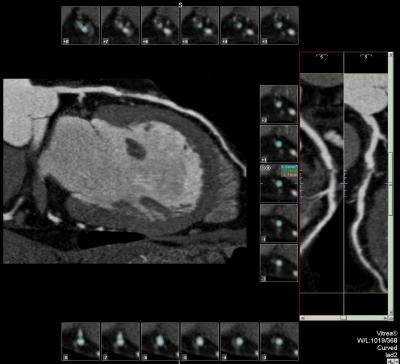

A study by an international team of cardiac imaging specialists, led by researchers at Johns Hopkins, concludes that sophisticated computed tomography (CT) scans of the heart and its surrounding arteries are almost as reliable and accurate as more invasive procedures to check for blockages.

Researchers say the newer, 64-slice CT scans, first introduced in the United States in 2005 and initially tested at Hopkins, won’t replace the need for inspecting arteries by cardiac catheterization, also known as coronary angiography, but the scans will help cardiologists more quickly rule out those who can skip the more invasive procedures. Studies suggest that as much as 25 percent of the 1.3 million cardiac catheterizations performed each year in the United States may be unnecessary.

In cardiac catheterization, a thin tube is threaded into a blood vessel in the groin area to the heart’s arteries, where a dye is released to produce a clear X-ray image of the beating heart and its arterial blood supply. In CT imaging, computer-driven machinery passes X-rays through the body, producing digitized signals or “slices” that are detected and reconstructed for a precise picture.

In CT imaging, each X-ray measurement lasts just a fraction of a second and represents a “slice” of an organ or tissue. The greater the number of detectors - the device being used in this study has a total of 64 - the better the picture resolution. A computer then uses these slices to reconstruct highly detailed, 3-D images of the heart and surrounding arteries. In cardiac imaging, a patient is injected with a contrast solution to increase the visual detail.